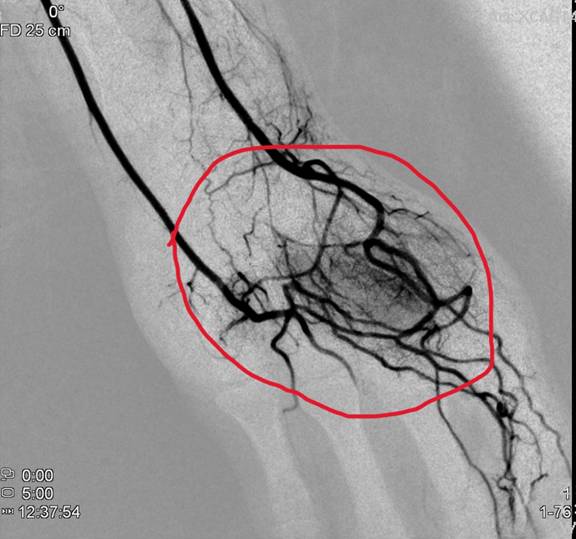

圖說:一名廚師患者因長期用手拿很重的鍋具,造成職業傷害,手部劇烈疼痛無法工作,從影像可以看出手腕及手掌有新生的異常「雲霧狀」血管密佈(圖中紅圈處)。